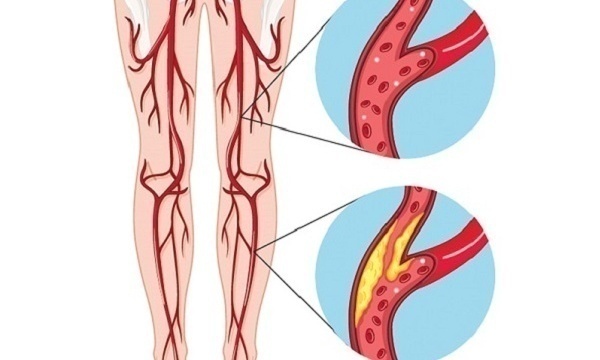

Изображения, связанные с атеросклерозом нижних конечностей и его лечением